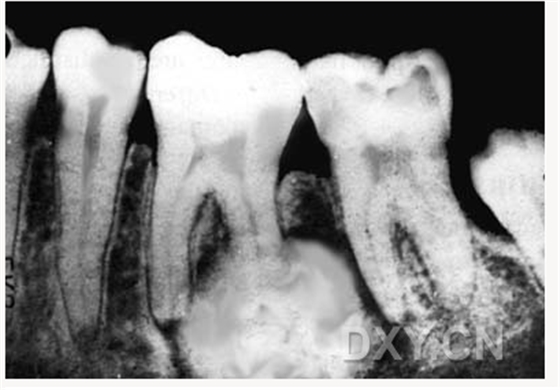

頜骨腫瘤

腺淋巴瘤[沃辛瘤

牙源性粘液瘤

頜骨骨折

多發(fā)頜骨囊腫

脂肪瘤

牙骨質(zhì)骨化纖維瘤